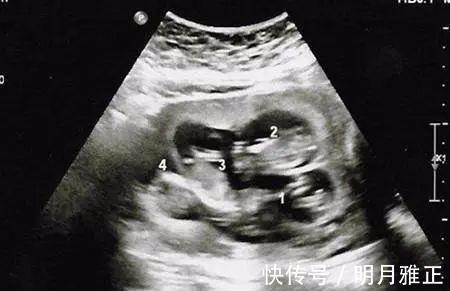

孕12周以后大如“临盆”,邻居亲朋都说不会是怀上双胞胎了吧,小蓉也只是笑笑,心想要是有就好了,当第一次产检时,医生却笑着恭喜说:“你是怀上了四胞胎了,我建议你最好减胎。”,全家人听完顿时愣住了。